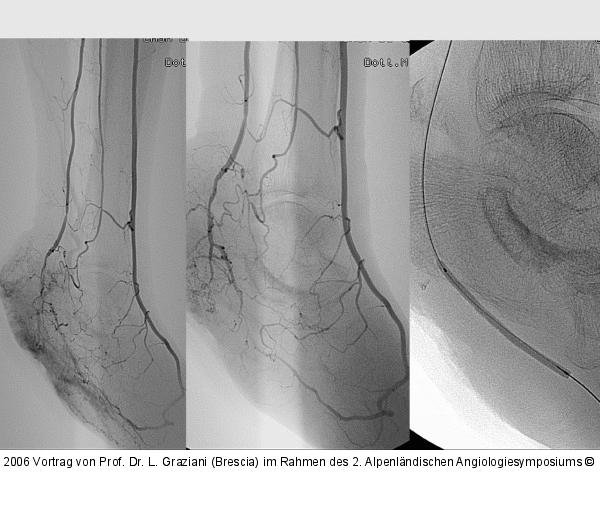

PTA of the foot arteries in diabetics: Extremities Extreme Angioplasty

Abbildung 25: Revaskularisation